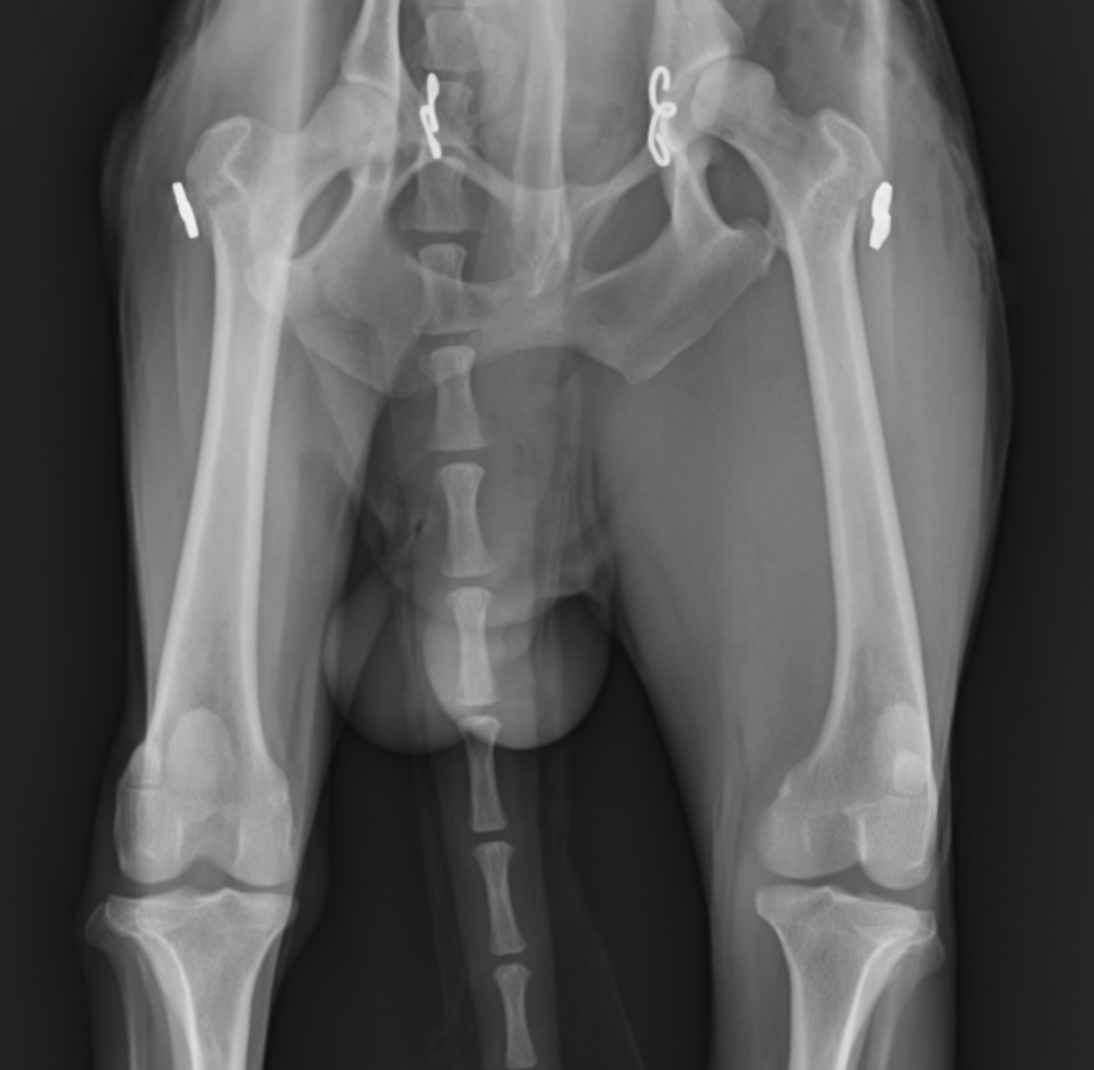

犬の股関節脱臼の整復(トグルピン法)

この子は遊んでいたら右後肢を挙上するとのことで来院され、レントゲン画像検査にて右股関節脱臼が確認されました。直ぐに手術を行い脱臼を整復しました。手術にはトグルピン法を行いました。

術後順調に回復していましたが、1ヶ月後には反対足を挙上するとのことで来院され、反対側の脱臼が確認されました。

そのため、すぐに反対足も同様の手術を行うことで脱臼を整復しました。

その後の経過は順調で、すぐに歩行開始し(術後2日目には普通に歩行可能でした)、その後再脱臼もせず、普段どおり生活しているとのことでした。